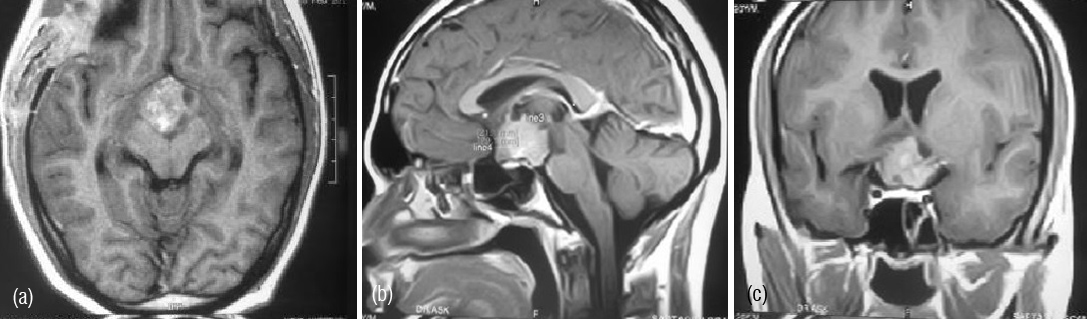

A 20 year old male medical student presented with history of blurring of vision of 4 months duration. Patient also had tingling and numbeness and weakness of right hand of 2 weeks duration. There was no history of headache, vomiting or seizures. On examination his higher mental functions were normal, there was weakness of right thenar muscles. Routine blood investigations, serum chemistry and hormonal assays were within normal limits. MRI brain revealed suprasellar lesion which was enhancing after contrast administration. Lesion was causing compression over optic chiasma.

Figure 1a,b,c: MRI -contrast enhancing mass lesion in sellar and suprasellar region.

Post operatively, MRI brain and screening of entire spine was done which revealed residual lesion in suprasellar region and interpeduncular cistern. Another intramedullary lesion at C3-C4 level was detected causing focal cord expansion and displacement of cord anteriorly suggesting metastasis.